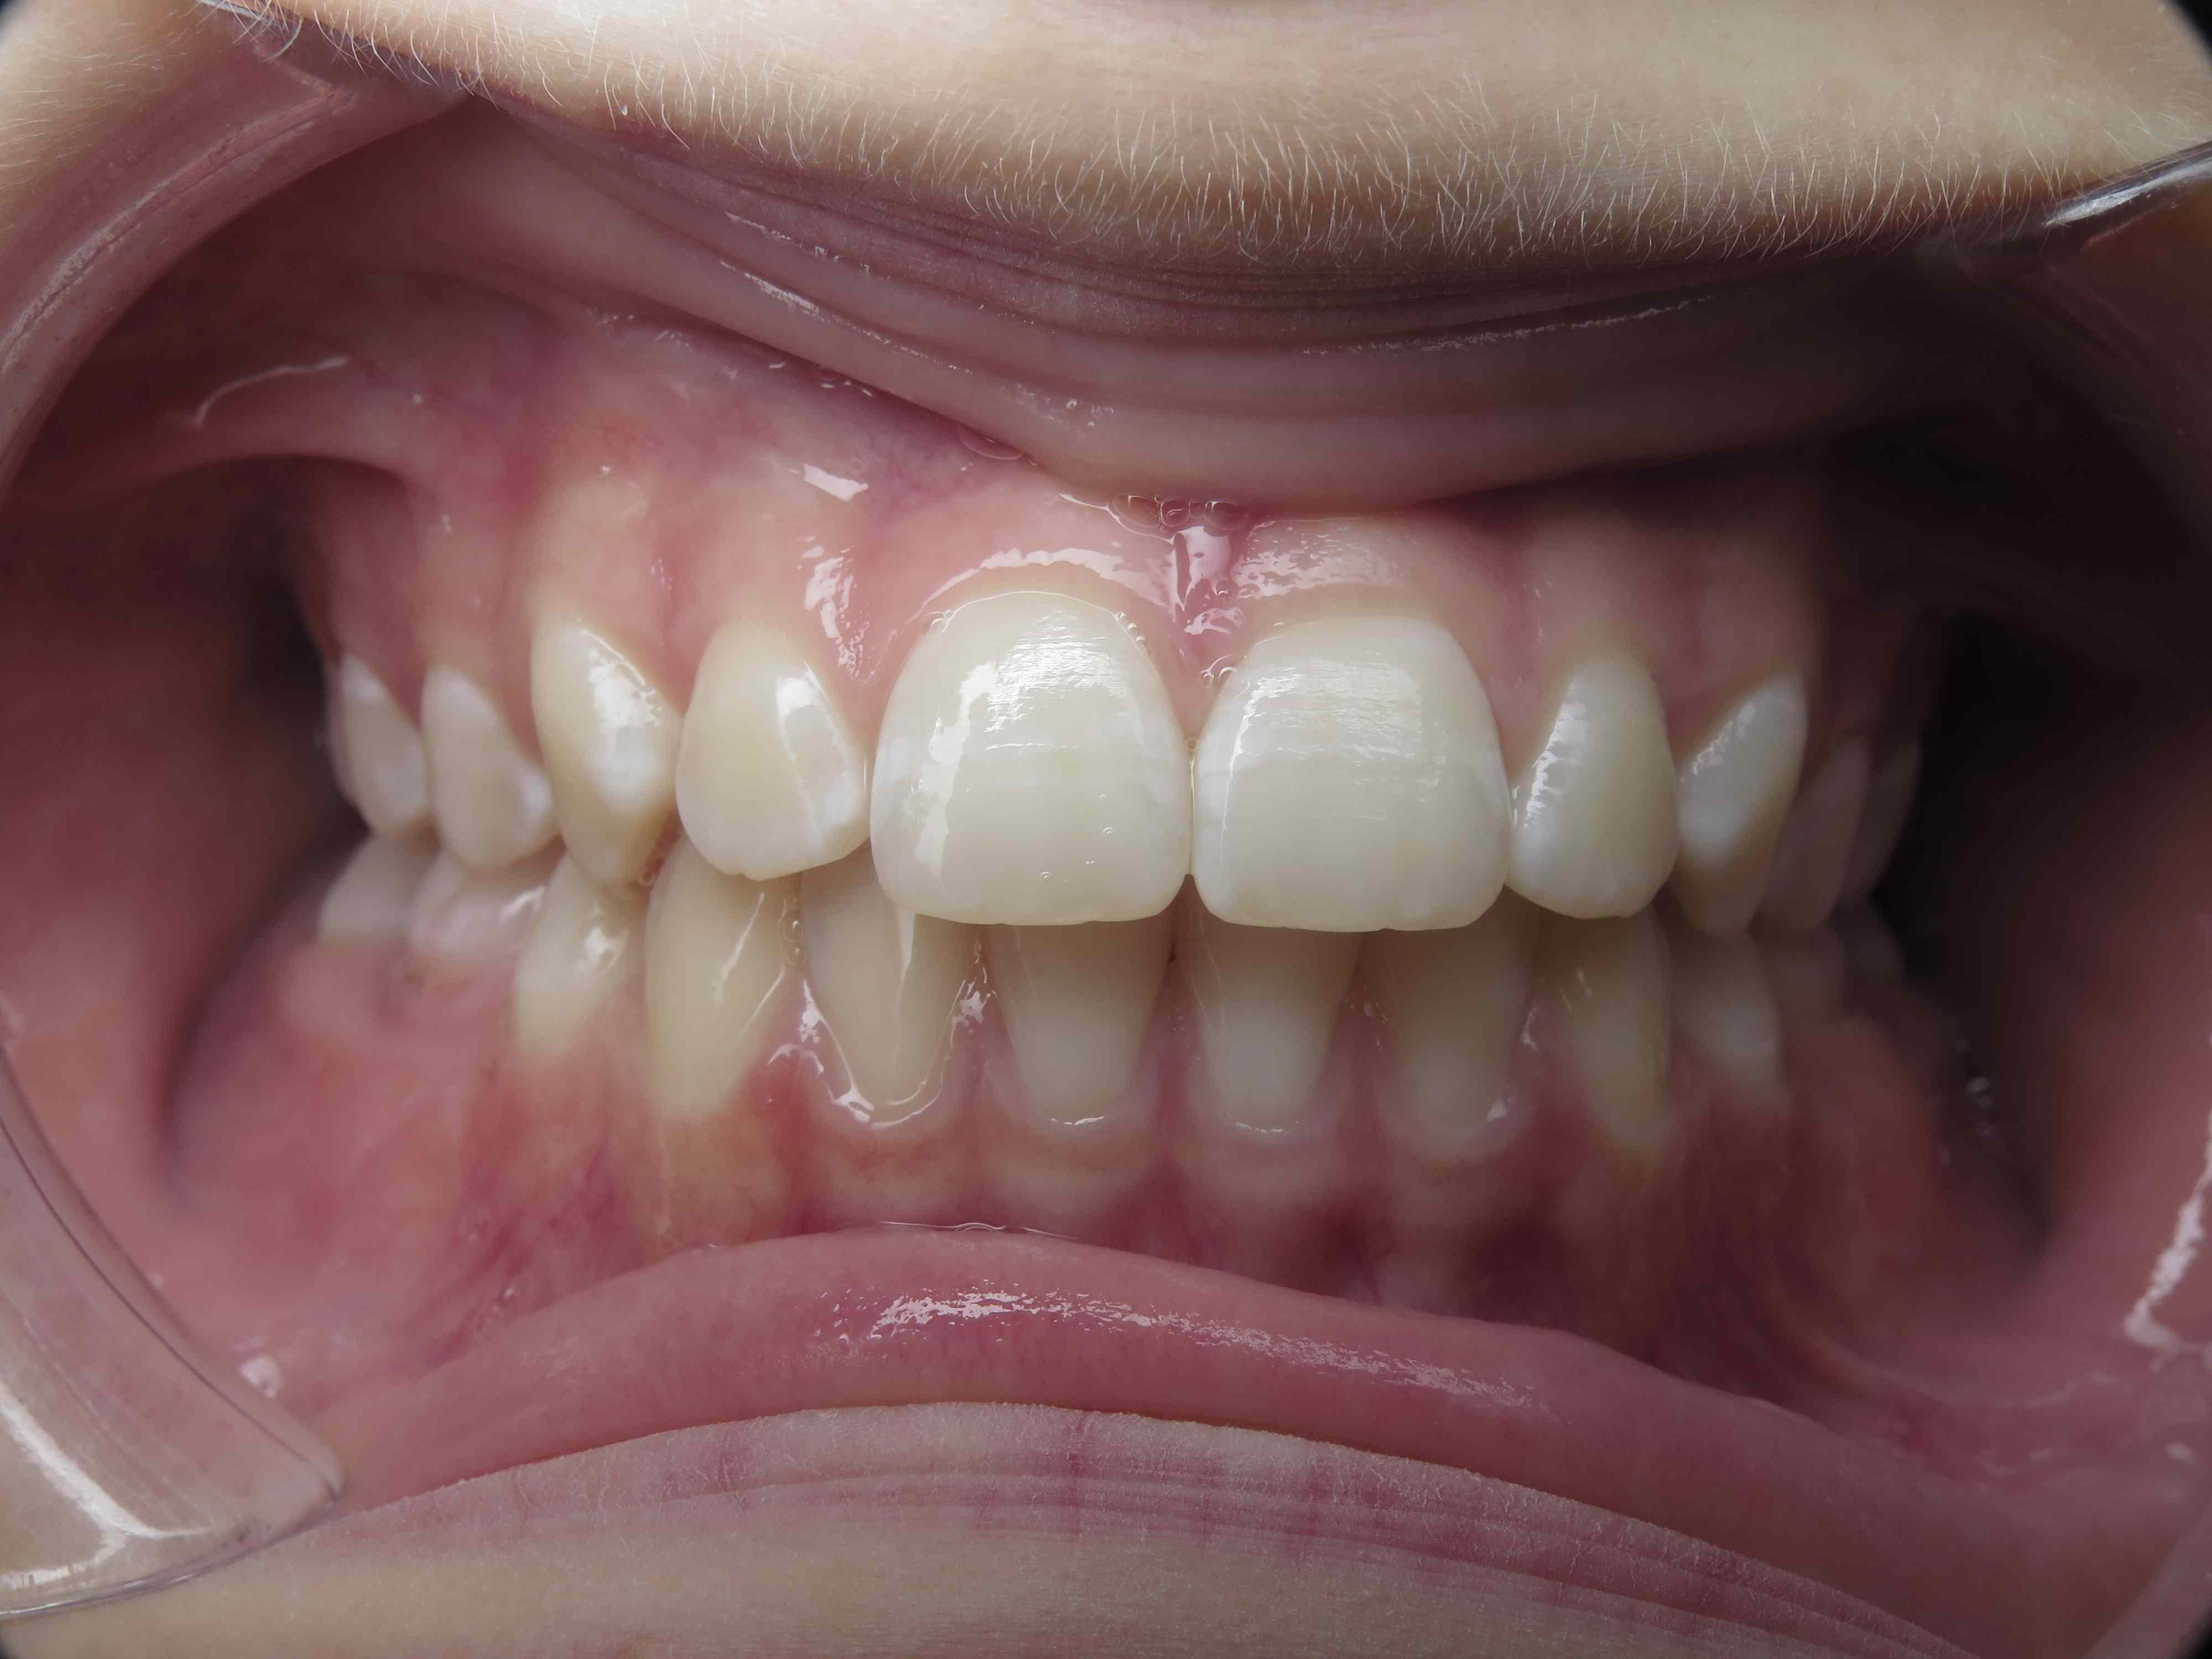

surveillance évolution de la dentition pendant 5 ans

appareillage multibagues traitement en cours

bilan début et en cours de traitement